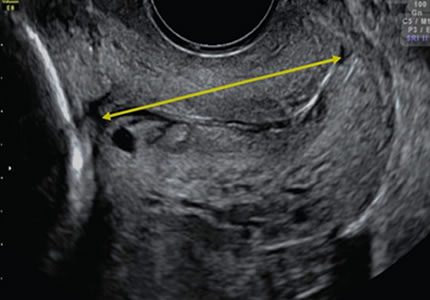

- A specialised assessment used to monitor the length of the cervix. This is a crucial check for patients at higher risk of preterm birth or those with a history of premature delivery, providing the data needed for your clinical team to manage your care safely.

- £109